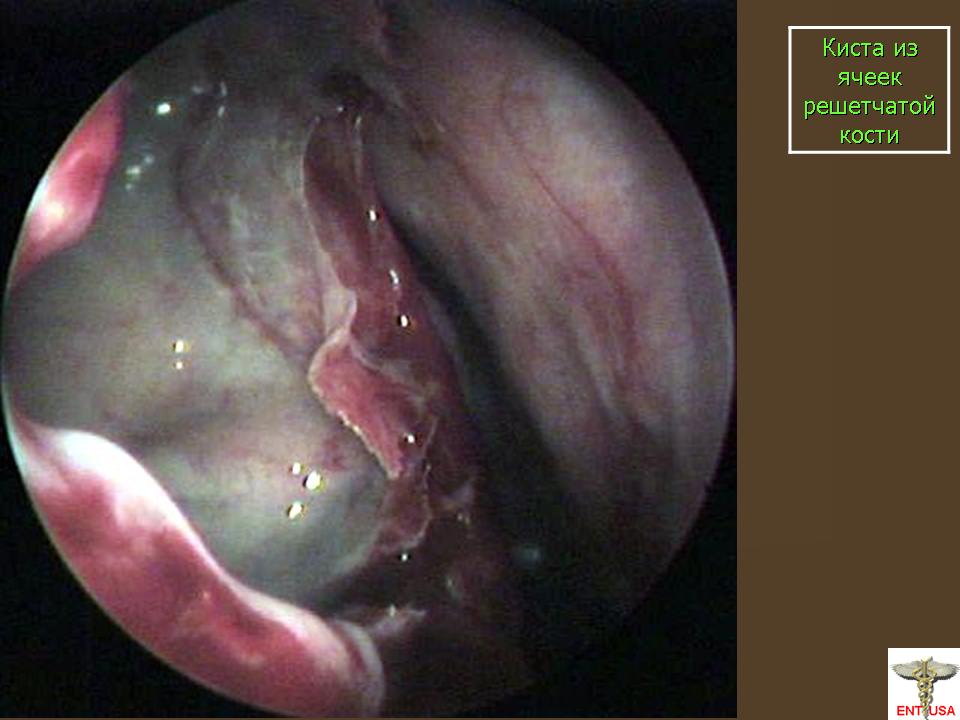

Кисты.